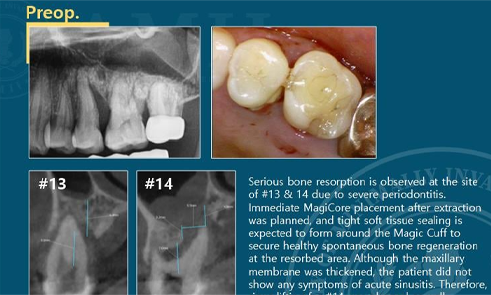

C.M.C with Immediate implantation

The CMC technique allows precise and controlled lifting of the sinus membrane.

Immediate implant in narrow anterior ridge

Magicore implants need only 0.25 mm of buccal and lingual bone.